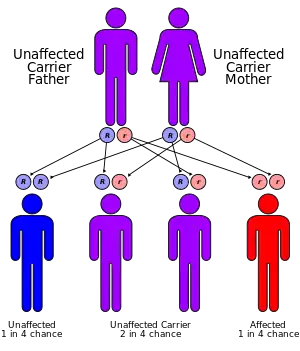

Inherited forms of leukodystrophy are usually the result of an autosomal recessive inheritance pattern, although dominant inheritance patterns are not unheard of, as in the case of adult-onset leukodystrophy.[13] This means that the affected allele is carried on an autosomal, or non-sex, chromosome and is masked by the dominant, unaffected phenotype. In other words, for an individual to inherit the leukodystrophy phenotype, he or she must carry two of the recessive, mutant alleles. Krabbe disease and metachromatic leukodystrophy (MLD) are two of such type. MLD is found on human chromosome 22 at position q13.31.[14] Another type of inherited leukodystrophy is X-linked adrenoleukodystrophy (X-ALD). As its name implies, this type of leukodystrophy is the result of a mutation found on the X-chromosome. It is also carried in a recessive pattern. The X chromosome is a sex chromosome, and since women have two "chances" of acquiring a normal X chromosome (one maternal x, one paternal x), and males only one chance (one maternal x), this disease is more likely to be seen in males than in females. The mutation resulting in adult-onset leukodystrophy is mapped at 5q23.[13]

Currently, no research has shown a higher prevalence of most leukodystrophy types in any one place around the world. There is, however, a higher prevalence of Canavan disease in the Jewish population. One in 40 individuals of Ashkenazi Jewish descent are carriers of Canavan disease.[28] This extrapolates to roughly 2.5%. Additionally, due to their autosomal recessive inheritance patterns, there is no significant difference found between males and females for most types of leukodystrophy, including but not limited to metachromatic leukodystrophy, Krabbe disease, Canavan disease, and Alexander disease. The one exception to this is any type of leukodystrophy carried on a sex chromosome, such as X-linked adrenoleukodystrophy, which is carried on the X-chromosome. Because of the inheritance pattern of X-linked diseases, males are more often affected by this type of leukodystrophy, while female carriers are often symptomatic, though not as severely affected as males.[29]